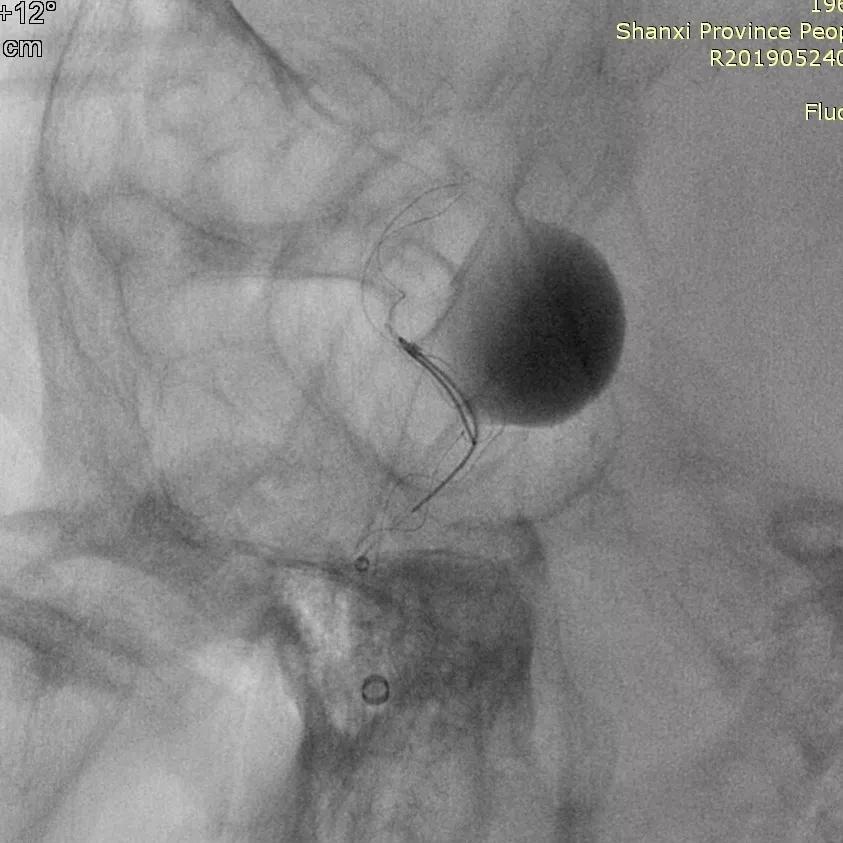

全脑血管造影可见右侧颈内动脉颈段末段夹层动脉瘤。

Traxcess 14微导丝导引Headway 17支架导管,远端顺利送入右侧颈内动脉远端,尾部连接Y阀1个,压力带1个(非肝素)。

经支架导管,置入Tubridge® 4.5×35mm,顺利释放,位置良好。

复查造影,各血管及分支通畅,流速正常。手术结束。